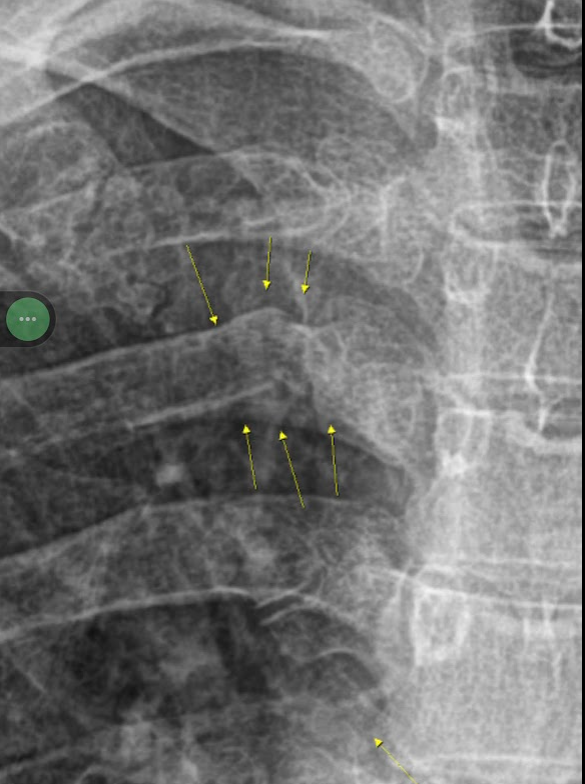

이튿날 병원에 가서 엑스레이를 찍어보니 부러졌네요.

그렇게 4주 진단이 나왔습니다.